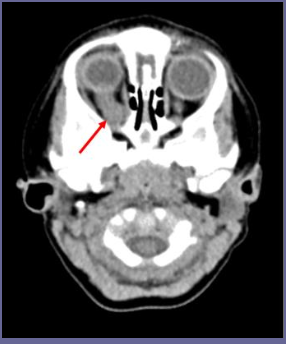

What are Astrocytoma?

star-shaped glial cells called astrocytes, arising from supporting cells in the CNS.

6 Characteristics of low grade (I-II) tumors

slow, relentless growth

frequently in the cerebellum

present with long history of non-specific symptoms (headaches, seizures, visual/coordination issues, decreased school performance)

well circumcised and solid, often with a cystic component

treatment includes complete surgical resection and chemo; possible radiation

good prognosis